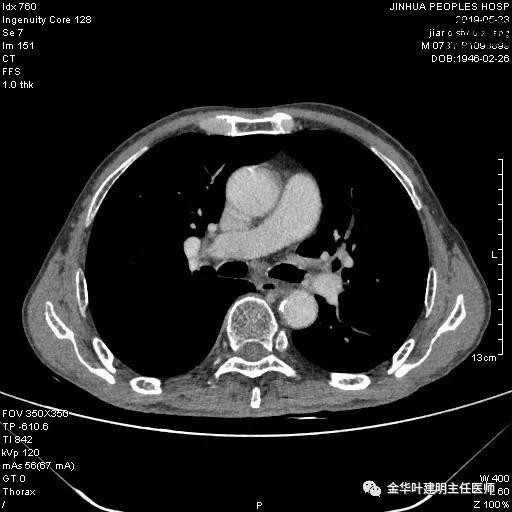

患者,男性,73岁,金华人。因“咳嗽咳痰伴胸闷2月,检查确诊左肺癌1周”入院。气管镜: 气管支气管内较多脓性分泌物,左肺上叶前段管腔新生物,局部活检、毛刷。气管镜病理:(左肺活检)鳞癌。阅胸部CT见左上叶开口处新生物,考虑需左上叶袖式切除及淋巴结清扫。具体CT表现如下:

术前检查冠脉CT示:左冠前降支近段多发钙化斑块伴管腔重度狭窄(约85%),建议DSA检查。但追问病史以往平时无胸痛或胸闷症状,运动试验提示可疑阳性(上斜型压低),活动后胸闷气闭症状不明显,既往否认高血压、糖尿病。所以经过心内科会诊讨论,认为还是可以进行手术。术前冠状动脉CT示: